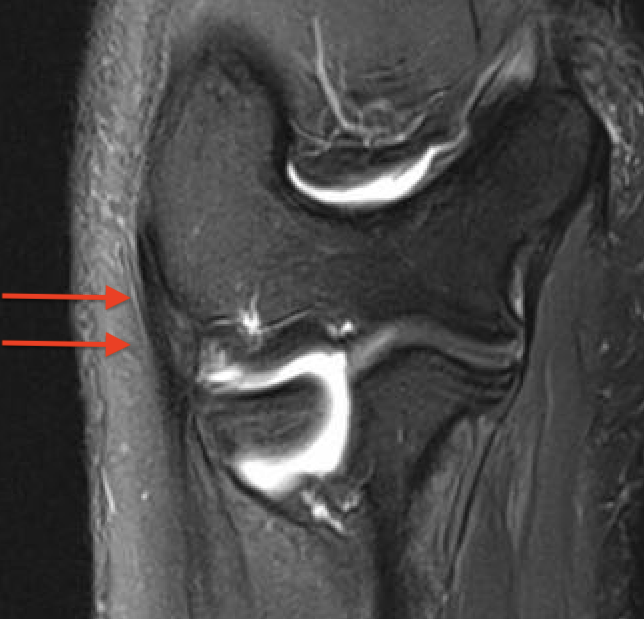

MRI

Normal

PRLI

Subtle instability of the radiocapitellar joint